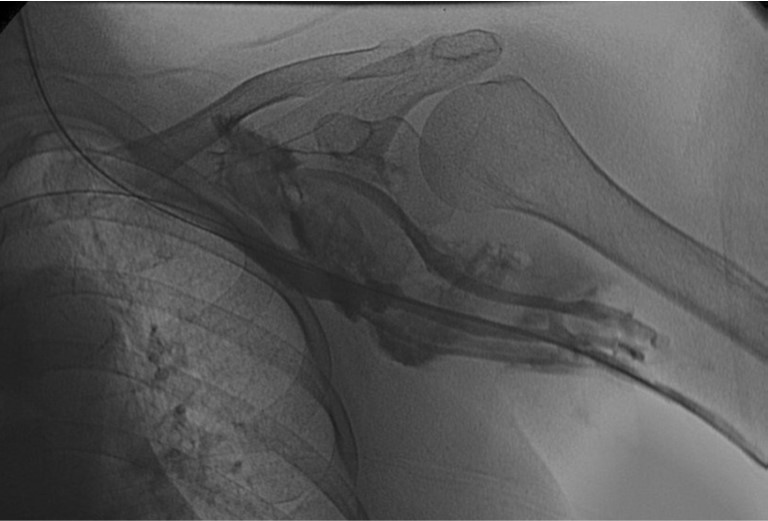

환자의 AV fistula는 초음파상 total thrombotic occlusion 된 상태였으며 시술 전 urokinase 100000 unit를 사용하여 thrombolysis and aspirated thrombectomy를 시행하였다. 그 후 시행한 shuntogram(Fig. 1) 상 left basilic vein 의 total ocdusion을 보이며 초음파상 remant vein의 크기는 1mm 이하로 확인되었다. 투시하에서 확인되는 outflow vein은 없었기에 초음파 유도하에 5 Fr Kumpe catheter(Soft-Vu, AngioDynamics, USA, NY) 에 0.035’ straight-tip guide wire(Terumo, Tokyo, Japan)를 사용하여 막힌 left basilic vein으로 15cm 이상 진행하였으며(Fig. 3), 4mm balloon (synergy, Boston, Ireland)를 사용하여 blind angioplasty를 하며 true lumen으로의 진행을 시도하였으나 실패하였다(Fig. 4). 더 이상의 antegrade로의 접근은 어려울 것으로 판단하여 regrograde approach를 위하여 left internal jugular vein 을 초음파 유도하에 9Fr sheath( Accu-Sheath, Sungwonmedical, Korea, Cheongju)을 사용하여 access 하였다. (Fig. 5A) 그리고 5Fr Cobra & sherpherd hook catheter (A&A M.D., Korea, Sungnam) 를 이용하여 left axillary vein으로의 접근을 시도하였다(Fig. 5B).

Fig. 1.

Occlusion state of left basilica van with collateral flow